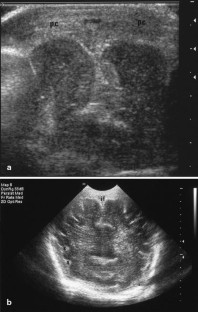

The purpose of this paper is to describe brain pathology in neonates after major traffic trauma in utero during the third trimester. Our patient cohort consisted of four neonates born by emergency cesarean section after car accident in the third trimester of pregnancy. The median gestational age (n=4) was 36 weeks (range: 30–38). Immediate post-natal and follow-up brain imaging consisted of cranial ultrasound (n=4), computed tomography (CT) (n=1) and post-mortem magnetic resonance imaging (MRI) (n=1). Pathology findings were correlated with the imaging findings (n=3). Cranial ultrasound demonstrated a huge subarachnoidal hemorrhage (n=1), subdural hematoma (n=1), brain edema with inversion of the diastolic flow (n=1) and severe ischemic changes (n=1). In one case, CT demonstrated the presence and extension of the subarachnoidal hemorrhage, a parietal fracture and a limited intraventricular hemorrhage. Cerebellar hemorrhage and a small cerebral frontal contusion were seen on post-mortem MRI in a child with a major subarachnoidal hemorrhage on ultrasound. None of these four children survived (three children died within 2 days and one child died after 1 month). Blunt abdominal trauma during pregnancy can cause fetal cranial injury. In our cases, skull fracture, intracranial hemorrhage and hypoxic-ischemic encephalopathy were encountered.